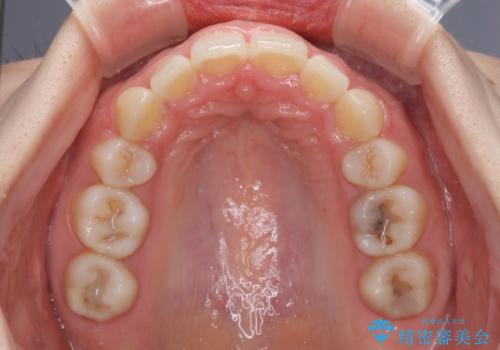

- 前歯のデコボコと上顎の前突感による口の閉じにくさを気にして来院された患者様です。

目立たない装置を希望されたので、上顎が裏側装置のハーフリンガルを選択し、上下左右の小臼歯(計4歯)を抜歯して矯正治療を行うこととしました。